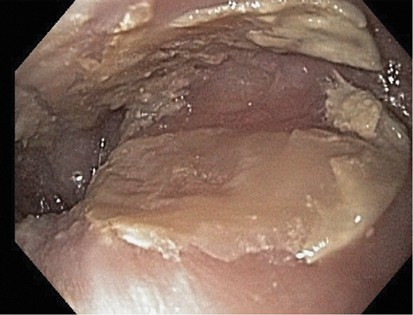

By definition, all patients in this study had endoscopic white plaques or membranes (Figures 1 and 2). The locations of the white plaques or membranes were specifically stated in the endoscopy reports of 26 of the 31 sloughing esophagitis patients (Table 2). Distal esophageal location for the endoscopic abnormalities was significantly more common than other sites (P<0.002). When the middle or proximal esophagus was involved, it was generally part of diffuse endoscopic abnormalities, rather than as localized disease. Additional endoscopic findings were infrequent and nonspecific, and included erythema beneath the white membranes in two patients, rings in two patients, distal narrowing in one patient, nodular mucosa in one patient, hiatal hernias in four patients, an irregular Z-line in one patient, and distal salmon-colored mucosa that was not biopsied in one patient. One additional patient had a large esophageal diverticulum containing pill fragments.